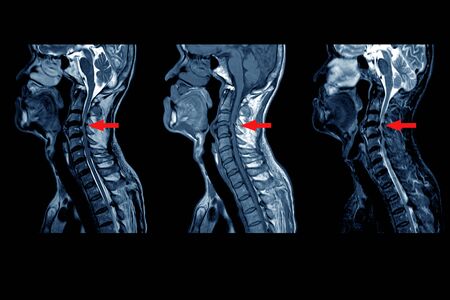

Hernia discal cervical

Cuando tenemos una hernia cervical puede ocurrir que esta comprima los nervios o la médula espinal provocándonos dolor, alteraciones motoros y sensitivas. Para quitar la hernia es necesario quitar el disco intervertebral lo que genera una inestabilidad, con el tiempo el espacio intervertebral se colapsa y es necesario realizar una artrodesis cervical.

Mielopatía

La mielopatía es una daño medular a nivel cervical provocado habitualmente por una compresión que puede estar provocado por una hernia, o por el crecimiento óseo que se produce en la espondiloartrosis. Del mismo modo que pasaba con la hernia discal, para descomprimir la médula es necesario quitar el disco intervertebral y por tanto se necesita realizar una artrodesis cervical.